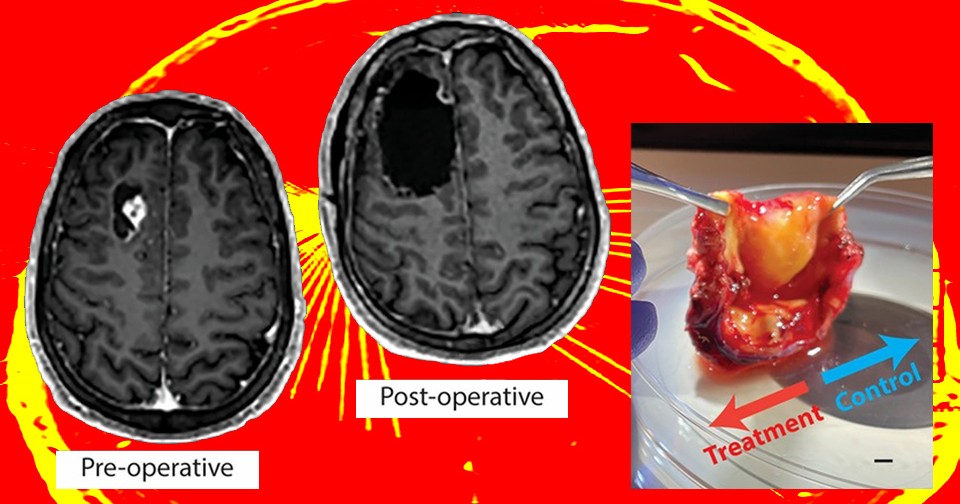

В своей новой работе Надер Санай (Nader Sanai) и его коллеги из неврологического института Барроу в США провели первые клинические испытания сонодинамической терапии на людях для проверки безопасности метода. В исследовании приняли участие 9 человек с рецидивирующей глиомой, которые получили 5-ALA и затем подверглись воздействию нацеленного ультразвука разной интенсивности. Спустя четыре дня их опухоли вырезали хирургическим путем. В качестве контроля использованы области мозга тех же пациентов, которые не подвергались воздействию ультразвука. По итогам клинических испытаний ученые обнаружили умеренные кратковременные побочные эффекты, связанные с воздействием ультразвука (головная боль, тревожность, тошнота), но никаких тяжелых последствий они не отметили.

Авторы исследования оценили и эффективность процедуры для генерации активных форм кислорода, сравнив обработанные ультразвуком и контрольные участки образцов опухолей, полученных в ходе операции. Несмотря на то, что авторы отмечают присутствие «умеренного» эффекта, ожидаемой дозозависимости и стабильности результатов тестов не наблюдалось. Маркеры окислительного стресса были стабильно увеличены в тестовых образцах только в группе из трех пациентов, получивших ультразвук минимальной интенсивности. Поскольку никаких серьезных побочных эффектов ученые не обнаружили, они планируют в дальнейшем сконцентрироваться над оптимизацией протокола, который бы позволил сделать процедуру не только безопасной, но и эффективной, как в случае с мышами.